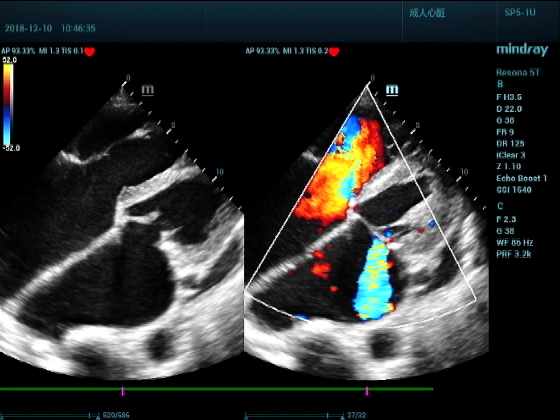

男,81岁,全身浮肿来住院

超声可见:左房,右房,右室明显增大,主肺动脉及右肺动脉增宽,二尖瓣中度反流,三尖瓣重度反流,肺动脉轻度高压,心律不齐

心包积液盆腔积液。淤血性肝增大,肝静脉增宽。(右心衰声像改变)